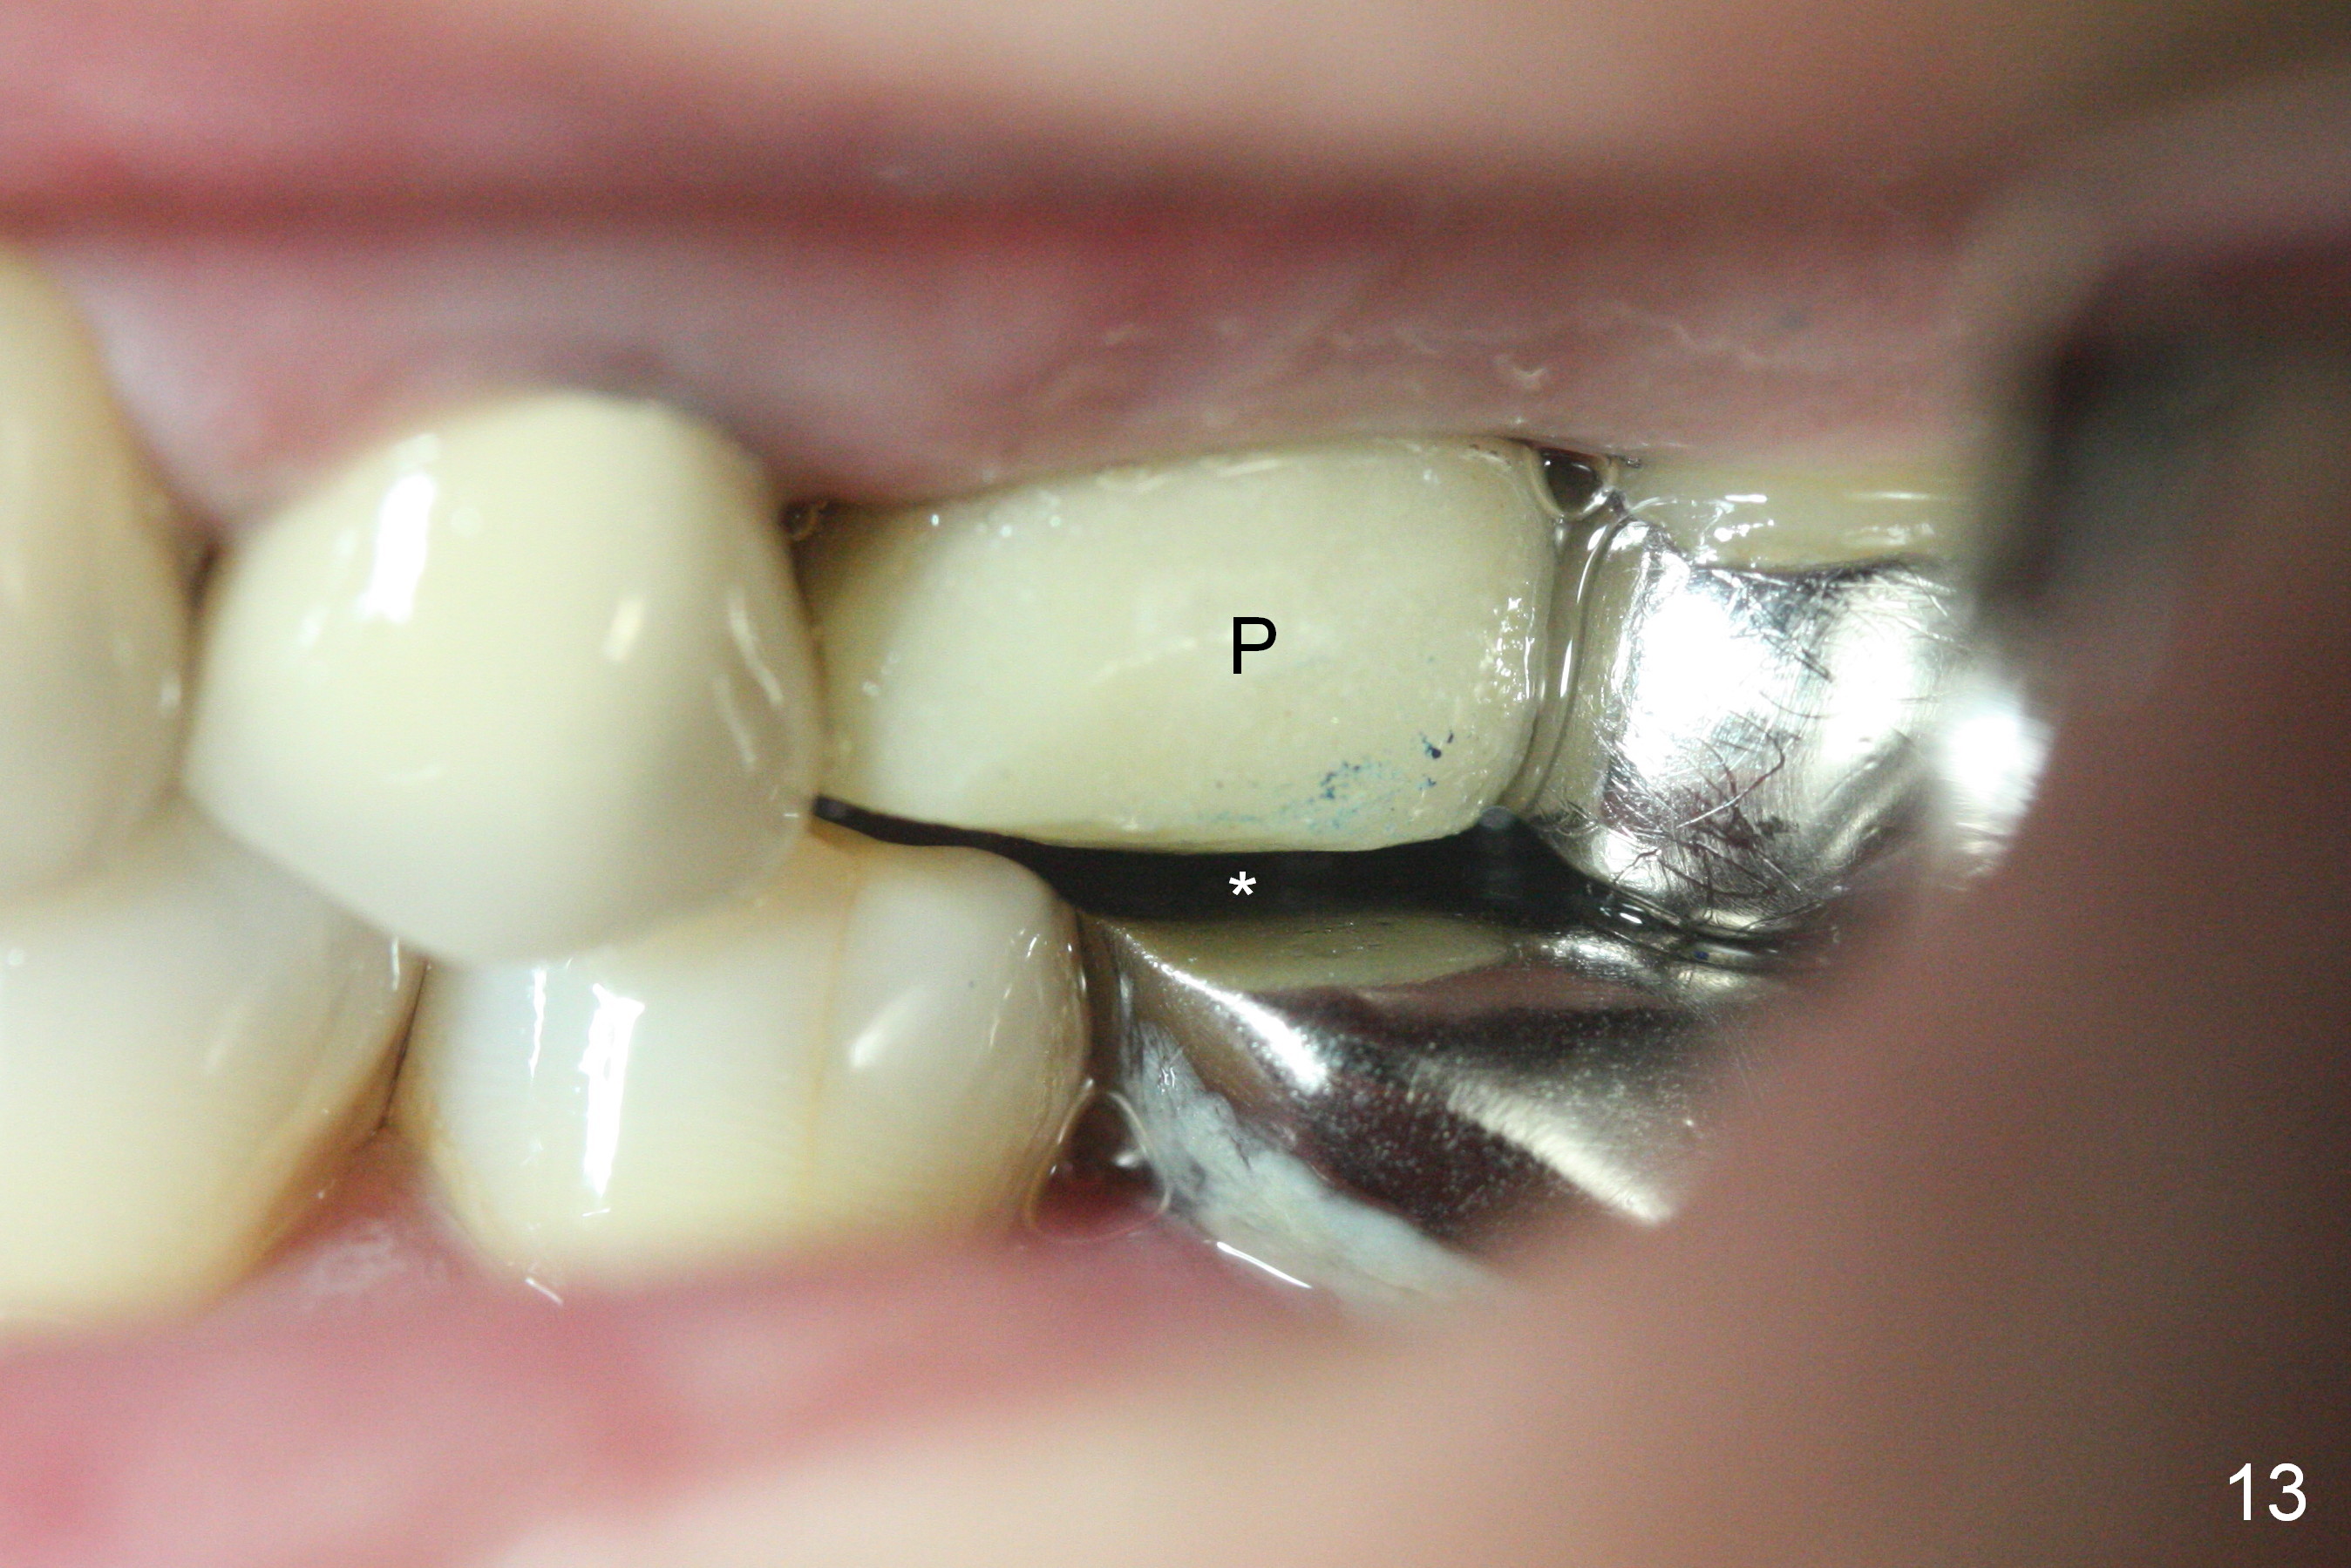

The patient is doing well 9 days postop.  The immediate provisional is loose and over-sized.  It is removed for trimming and reline; the socket and bone graft (Fig.8 *) are healing.  It appears that an angled abutment is required next time of provisional revision.  When an angled abutment is being placed 23 days postop (Fig.9), it appears to wiggle the implant due to its long leverage.  Instead a healing abutment is placed.  The implant is unstable 4.5 months postop with seemingly excessive bone-implant gap (Fig.10 <).  The 5.5x9 mm implant is removed.  A 5x17 mm tap is used to change the trajectory and sinus lift, followed by 6x17 one (Fig.11).  Finally a 6x14 mm tissue-level implant is placed with insertion torque > 50 Ncm (Fig.12; vs. <20 Ncm (Fig.7,10)) and improved trajectory.  An immediate provisional is fabricated to prevent the mesial drifting of the tooth #15 (Fig.13 P (*: occlusal clearance)).  By using the taps and placing the longer implant, the sinus lift is more obvious (compare Fig.10 and 12 (*)).  Sinus lift remains evident 3.5 months postop (Fig.14) with apparently osteointegration (Fig.15).